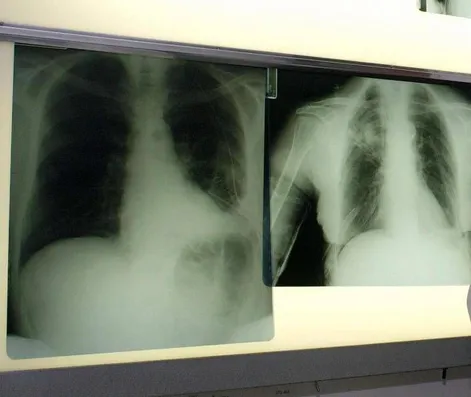

Il tumore al polmone - ricorda l'azienda in una nota - continua a essere una delle neoplasie più diffuse e letali in Italia e nel mondo. Ogni anno, solo in Italia, vengono diagnosticati 44.831 nuovi casi. Circa il 12% riguarda il carcinoma polmonare a piccole cellule, una forma aggressiva e a rapida progressione, per la quale le opzioni terapeutiche sono rimaste a lungo limitate. Negli ultimi anni, tuttavia, i progressi nel trattamento dello Sclc hanno aperto nuove prospettive. Tra questi, un composto sintetico di origine marina - estratto dall'invertebrato Ecteinascidia turbinata - che ha dimostrato risultati promettenti in combinazione come terapia di mantenimento in prima linea per i pazienti con Sclc in stadio esteso (Es-Sclc), una delle forme tumorali più aggressive e con maggiori bisogni clinici insoddisfatti. Come dimostrano i risultati dello studio di fase 3 IMforte, presentato lo scorso giugno all'Asco Annual Meeting 2025 di Chicago, il Congresso dell'American Society of Clinical Oncology, il composto sintetico di origine marina, in combinazione con immunoterapia, riduce del 46% il rischio di progressione della malattia o di morte, con una sopravvivenza mediana globale di 13,2 mesi rispetto ai 10,6 mesi con la sola immunoterapia.

"Il carcinoma polmonare a piccole cellule è una delle forme più aggressive e difficili da trattare di tumore del polmone - spiega Silvia Novello, direttrice della Struttura complessa a direzione universitaria di Oncologia medica dell'Ospedale San Luigi di Orbassano e professoressa ordinaria di Oncologia medica all'Università degli Studi di Torino - Nella maggior parte dei casi, la diagnosi avviene quando la malattia è già in fase avanzata e le opzioni terapeutiche a disposizione sono limitate. I risultati dello studio IMforte rappresentano un'importante novità: la nuova combinazione ha dimostrato un beneficio clinico significativo, con un miglioramento della sopravvivenza globale e della sopravvivenza libera da progressione. Si tratta di dati estremamente incoraggianti - sottolinea - che potrebbero cambiare concretamente l'approccio terapeutico per questi pazienti e aprire una nuova prospettiva di trattamento per una popolazione finora e per troppo tempo priva di alternative efficaci".